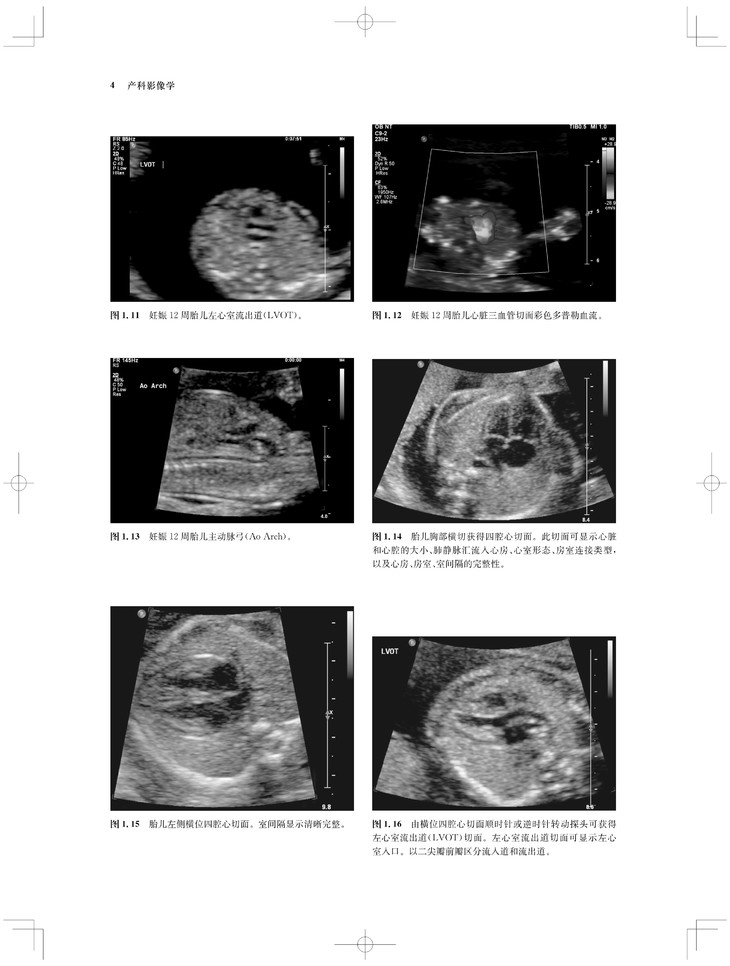

内容涵盖了胎儿宫内疾病的所有病种,从疾病的概述、流行病学、病因学、病理生理学,到临床表现、各类影像学技术的诊断和鉴别诊断,再到产前、产后的治疗和干预手段,都做了全面介绍,重点阐述了疾病的超声、X线、CT、MRI、PET、CT等影像学表现,以及诊断与鉴别诊断,并辅以大量标准化的影像学图片,图文并茂。

《产科影像学——胎儿诊断和监护》是Elsevier(Saunders)出版的“Expert Series”之一,由国际最顶尖的妇产科、生殖科、母胎医学和影像学专家共同编写,代表着该领域最顶尖的水平。书中配有大量典型影像图片,内容丰富全面,编写理念先进,侧重于疾病的影像学征象分析及鉴别诊断和诊断流程的制定,从临床思维上进行了更新;同时兼顾临床和病理医师,重点内容以列表、提要、要点的形式进行总结,提纲挈领,方便读者阅读、记忆。对于每天不断进行诊断与鉴别胎儿疾病的影像工作者、病理科和临床医师而言,具有重要的参考价值。